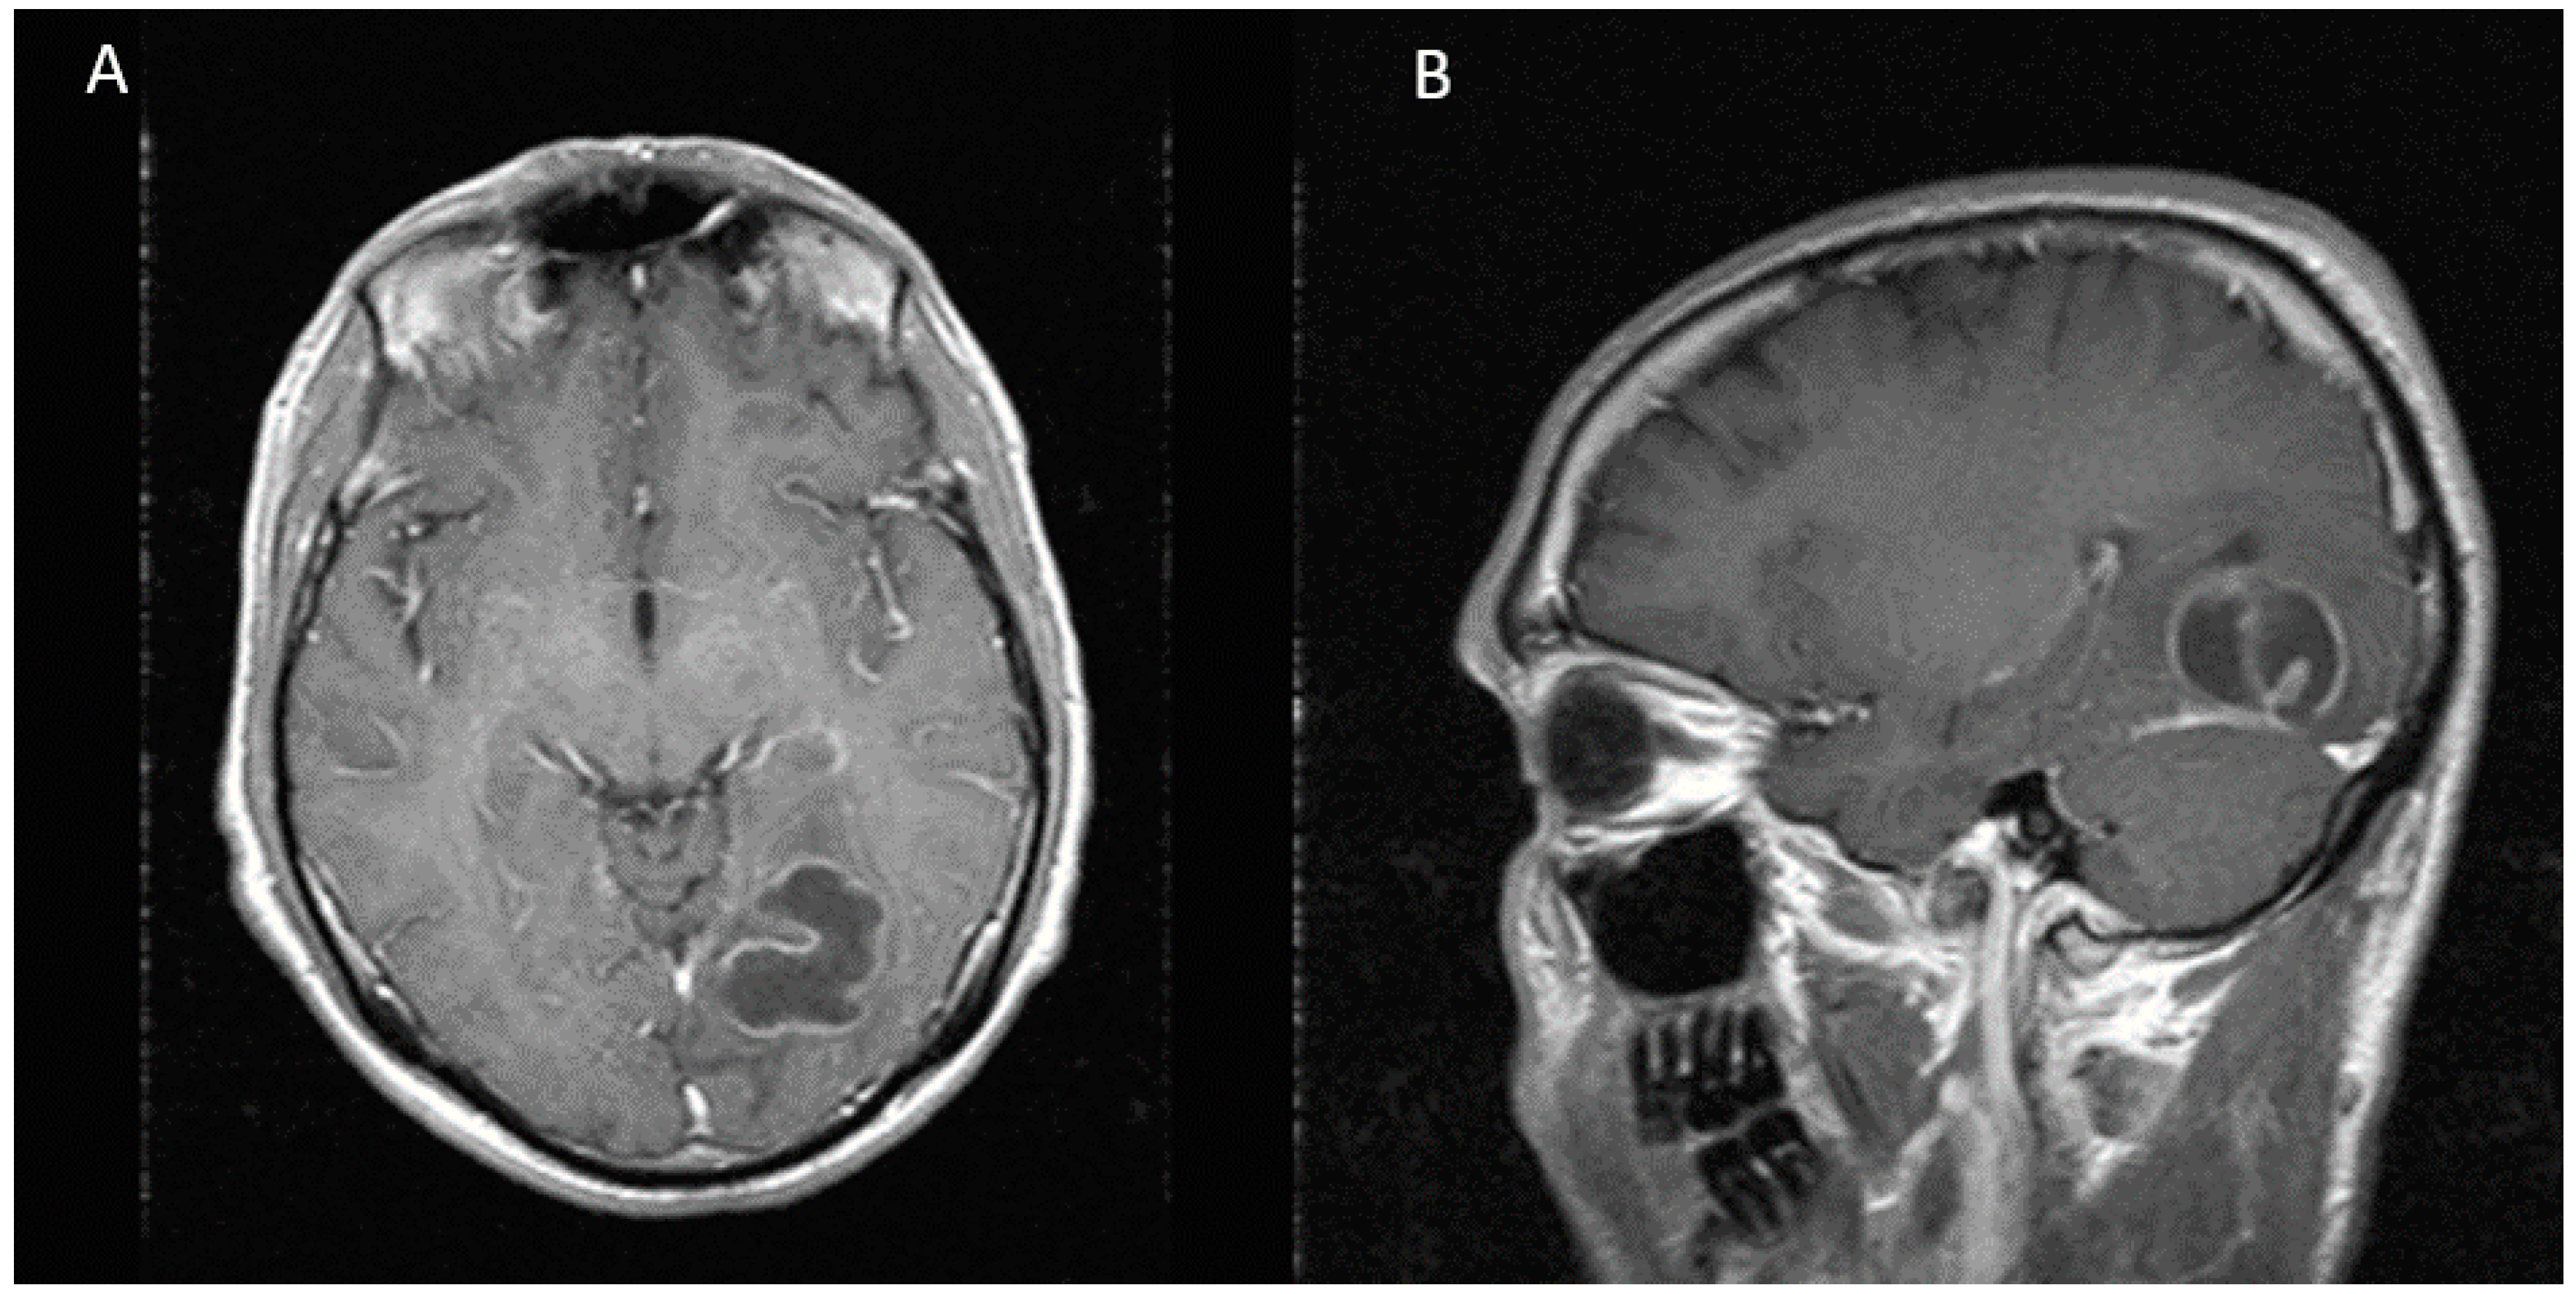

Figure 1.

MRI showing a multilobulated and multiseptated lesion of 31 × 31 × 26 mm with peripheral enhancement in the left occipital lobe. (A) Axial view (B) Sagittal view.